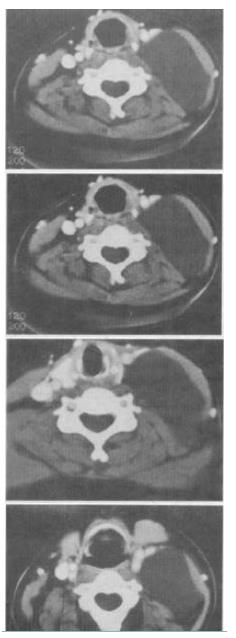

- 单项选择题 男,40岁,颈部出现无痛性囊性包块2年余,CT扫描如图所示,最可能的诊断是()。

A、淋巴管瘤

B、血管瘤

C、淋巴结肿大

D、神经源性肿瘤

E、颈动脉鞘瘤

- A